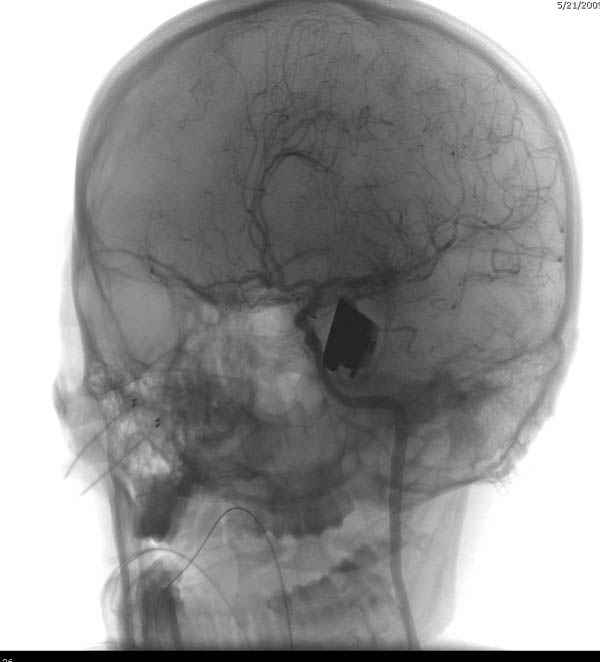

В своих выступлениях я рассказывал, что наши центры в мирное время по пенетрирующим травмам не уступает Ираку или Афганстану, и вот недавно к нам поступила больная 22 лет, травма "ножом в глаз" от бывшей подруги нынешнего "бой френда".

При поступлении в сознании, жаловалась на неприятные ощущения в глазнице.

По протоколу сделаны все необходимые исследования: рентген, ангиограмма с 3Д реконструкцией, где обнаружили что все жизненно важные сосуды не задеты, даже некоторые "сидят" изгибаясь на ноже.

Одним махом нож удалить не удалось, пришлось раскачать и потом двумя руками удалили нож. Рана без кровотечения, обработана и зашита.